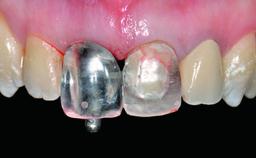

A 49-year-old female patient was referred for implant therapy to replace the upper right central incisor (tooth 11). The tooth had been assessed by an endodontist who diagnosed a vertical fracture of the root. The tooth had a hopeless prognosis and needed to be extracted. The patient was healthy and was not taking any medications. She was allergic to penicillin. The patient had high esthetic demands but her expectations were realistic. The extraoral examination revealed no facial asymmetries. The right temporomandibular joint demonstrated an opening click but was otherwise asymptomatic. The lip line was high with a significant gingival display.

Bone Augmentation Simultaneous|Vertical

Augmentation Materials Autogenous chips|Xenogenous|Membrane